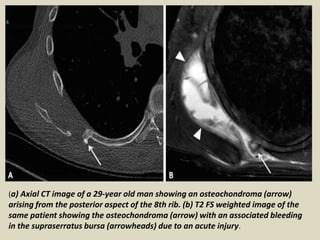

Computed Tomography

CT is indicated when an underlying osseous abnormality is suspected and plain films do not

reveal any abnormalities. Anatomical variations comprise the most common subgroup of

osseous abnormalities causing snapping scapula syndrome and include (a) an excessive

anterior curvature of the superomedial scapular angle rubbing across the ribs, (b) a

Luschka’s tubercle being a bony prominence at the supermedial angle of the scapula and

(c) a teres major process representing an anterior curvature towards the chest wall at the

inferior aspect of the scapula. It is important to realize that these anatomic variants are

commonly seen and increase the risk of snapping scapula, but do not cause symptoms in

the majority of people. Other common causes of snapping scapula include mal united

scapula- or rib fractures, reactive spurs and osteochondromas arising from the rib or

anterior surface of the scapula. Chondrosarcoma are a rare cause of snapping scapula and

are usually seen in an older age group

(a) Axial CT image of a 29-year old man showing an osteochondroma (arrow)

arising from the posterior aspect of the 8th rib. (b) T2 FS weighted image of the

same patient showing the osteochondroma (arrow) with an associated bleeding

in the supraserratus bursa (arrowheads) due to an acute injury.